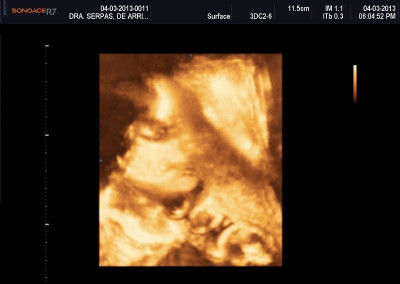

Varias ultrasonografías en 2D y 3D

Envíado por Dr. Nelson Menjívar Sarco